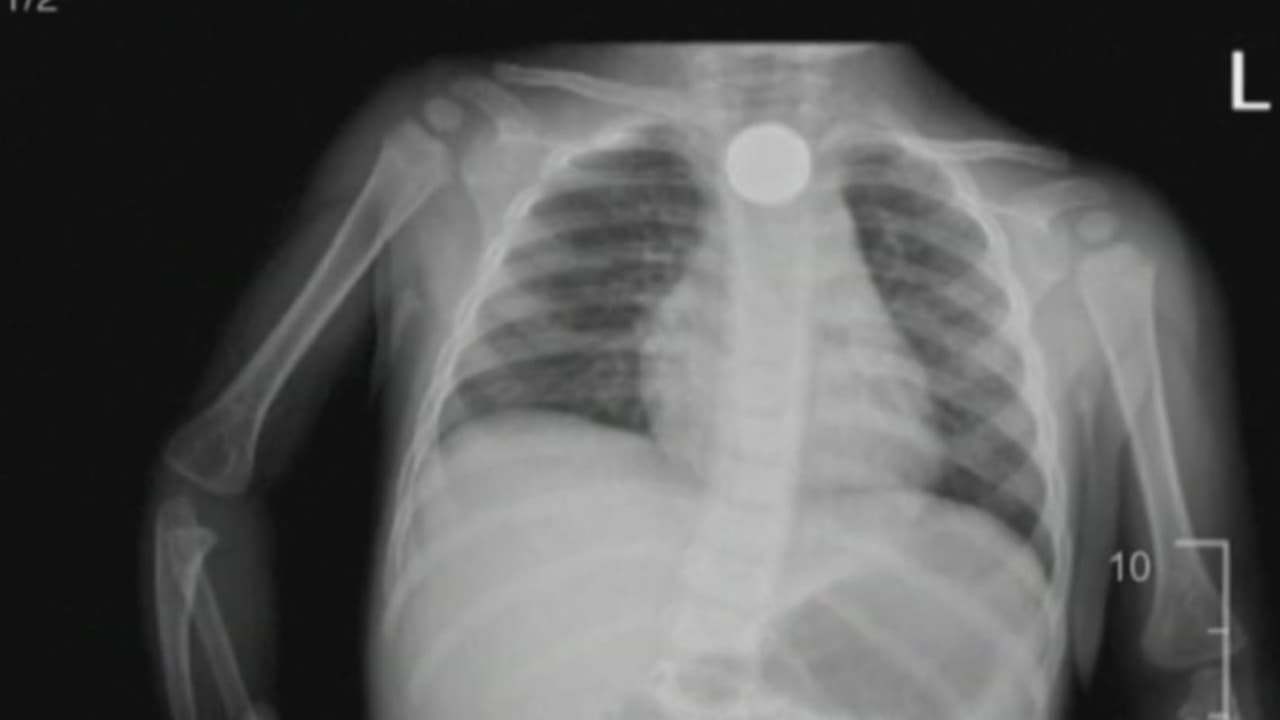

Un reporte de la Academia Americana de Pediatría indica que cada año, más de 3,000 niños en EEUU se tragan las pequeñas baterías redondas usadas en diversos dispositivos. Estas pilas de litio pueden causar daños permanentes o hasta fatales, por lo que Maity Interiano nos dice cómo evitar una tragedia en nuestra propia casa.